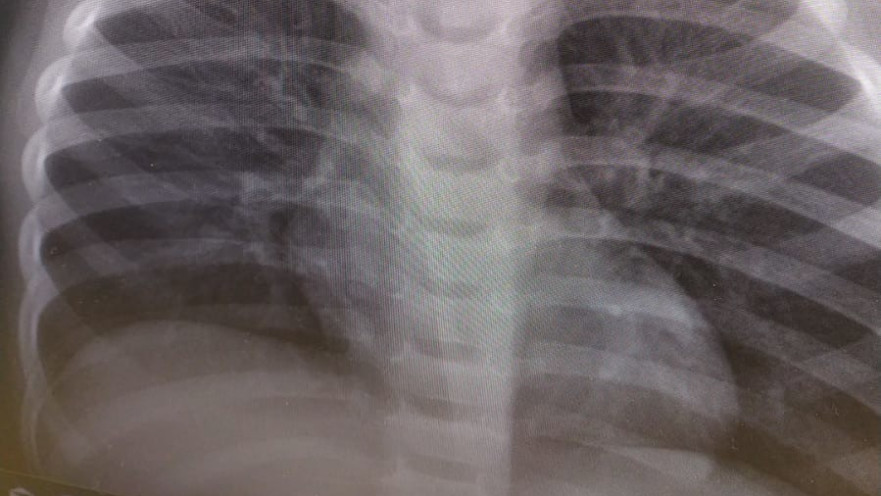

ד"ר אפרת אמיתי, רופאה בכירה במחלקה לרפואה דחופה בילדים בבית החולים הדסה הר הצופים ציינה: "לילא הגיעה לבית החולים עם תלונות של הקאות וחום. ברפואה דחופה עם ילדים אנחנו צריכים לחשוב על כל התרחישים האפשריים שיכולים להסביר את התסמינים שלפנינו. הבנו מאימה שאין סיפור של בליעת חפץ, אבל התשובות של בדיקות הדם שלה לא תאמו למה שהיא הייתה בטוחה שלא התרחש והבנו שאנחנו צריכים לבדוק כיוונים נוספים. אנחנו יודעים שלעיתים ילדים מצליחים לחמוק מעייני הוריהם, וגם כמה שניות בלבד מספיקות כדי לבלוע חפצים, ולכן לקחנו את לילא לצילום רנטגן מאותו הרגע הבנו שאנחנו במצב חירום, ראינו השתקפות של חפץ עגול בוושט העליונה והסימנים שאנחנו יודעים לזהות הצביעו על כך שזו סוללה. יצרנו קשר מיידית עם ד"ר לירון בירימברג-שוורץ שהייתה כוננית גסטרואנטרולוגיה ילדים באותו הערב והיא איששה לנו את החששות שאכן מדובר בסוללת כפתור. במקרה של סוללה בוושט צריך להוציאה בהקדם האפשרי כיוון שנזק משמעותי עלול להיגרם תוך זמן קצר. ידענו שלילא כבר יומיים מקיאה והסיבוכים עלולים להיות קשים".